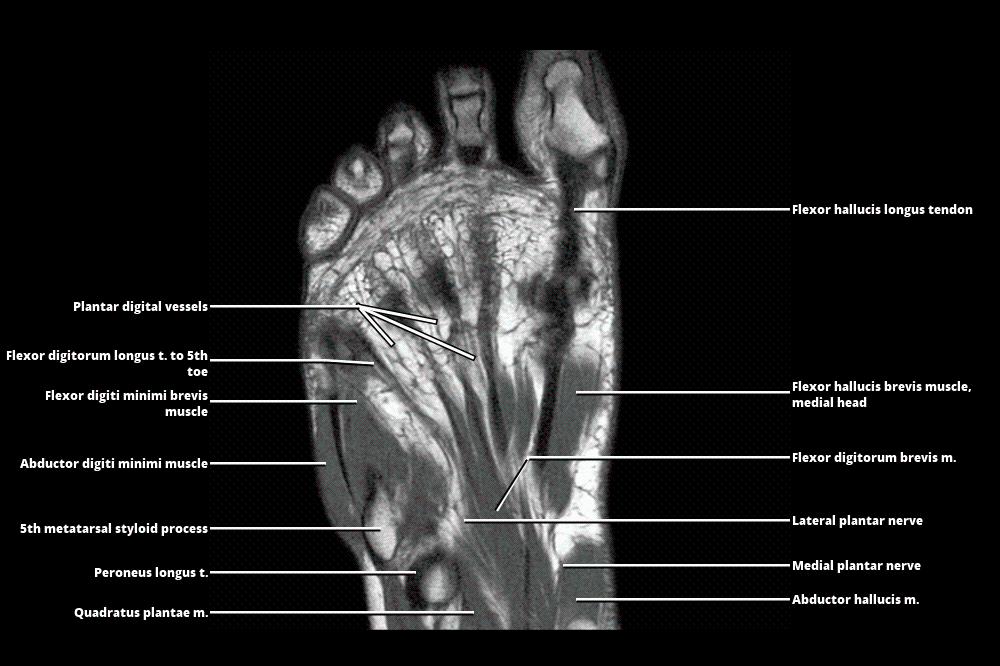

MRI Of The Foot | Radiology Key

radiologykey.com

radiologykey.com

mri foot radiology

Forefoot Mri Anatomy

mavink.com

mavink.com

Ankle And Foot | Radiology Key

radiologykey.com

radiologykey.com

foot ankle radiology fig radiologykey

Ankle And Foot | Radiology Key

radiologykey.com

radiologykey.com

foot ankle axial radiology medial sole lateral radiologykey

Ankle And Foot | Radiology Key

radiologykey.com

radiologykey.com

foot ankle radiology fig